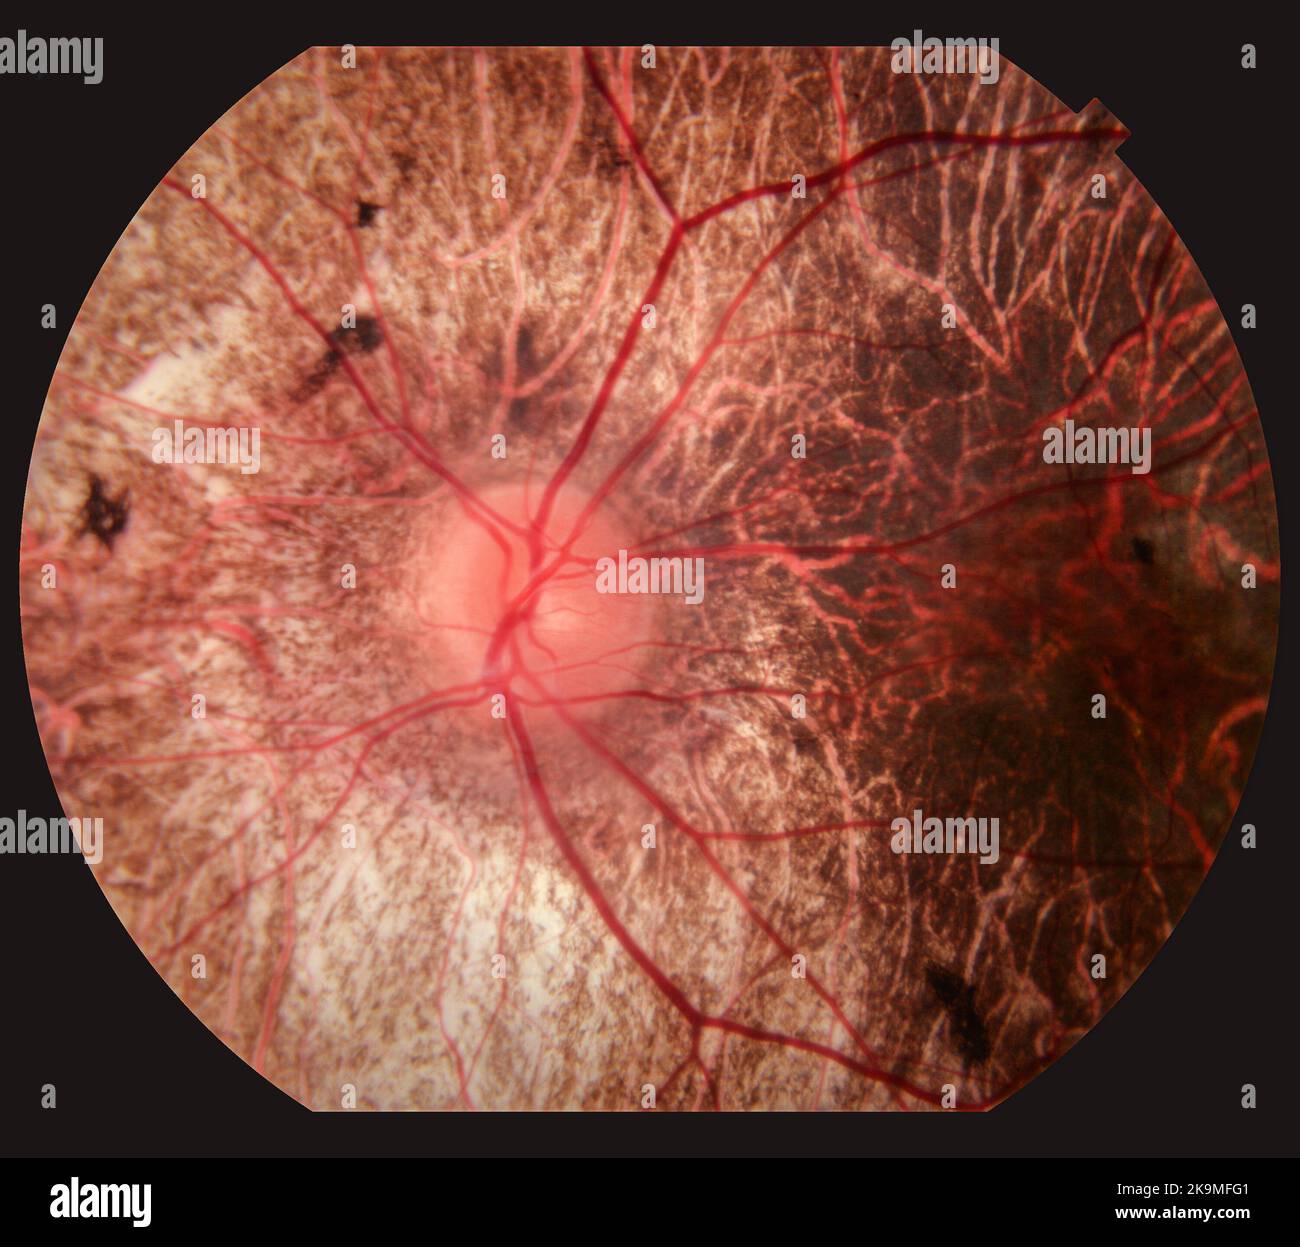

Photography of Human Eye Retina Stock Photohttps://www.alamy.com/image-license-details/?v=1https://www.alamy.com/photography-of-human-eye-retina-image487873457.html

Photography of Human Eye Retina Stock Photohttps://www.alamy.com/image-license-details/?v=1https://www.alamy.com/photography-of-human-eye-retina-image487873457.htmlRF2K9MFG1–Photography of Human Eye Retina